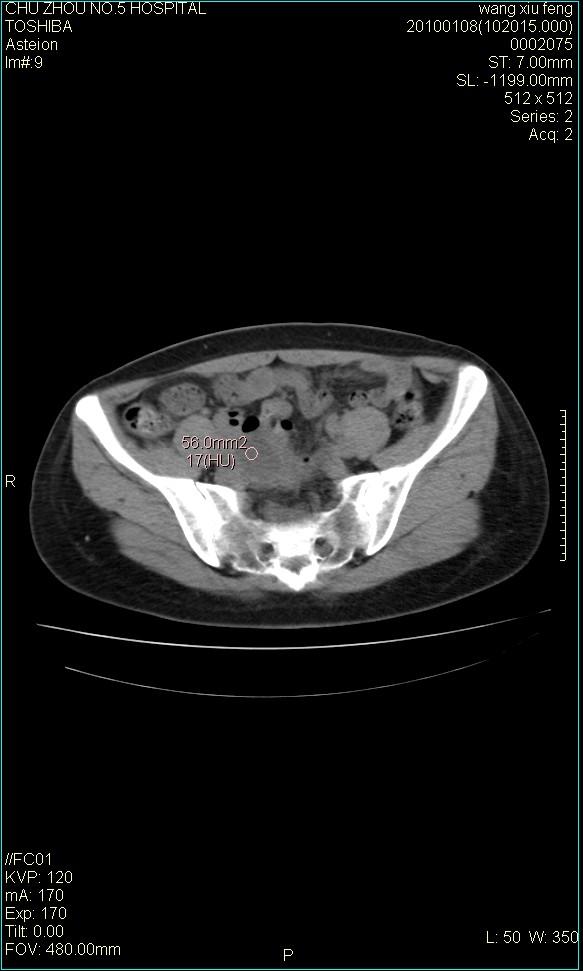

f-41,左乳腺ca术后4年,b超示:子宫右上方囊性包块约5.5*3.4cm,前日行胸部ct平扫未见明显异常。

考虑右侧卵巢囊腺瘤?

右侧卵巢囊肿或小囊腺瘤。

考虑右侧卵巢囊腺瘤?建议增强!

考虑右侧卵巢囊腺瘤。

考虑右侧卵巢囊性占位性病变(囊肿?囊腺瘤?)。